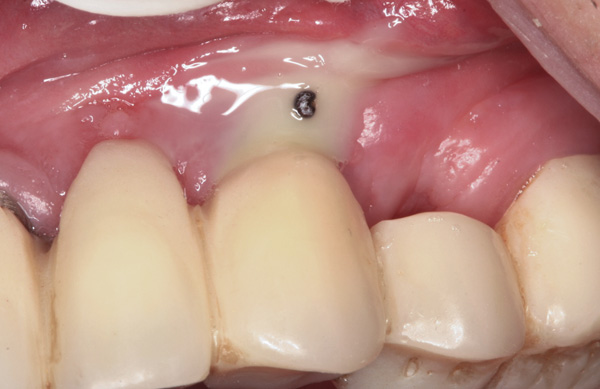

Suppuration is a cardinal sign of an infection, yet it may not be present. Pus is usually a thick viscous fluid that is often created in response to an infection. As the neutrophils die, they are destroyed by macrophages, thereby forming pus. Pus is usually white or yellow, but it can be red, green, or blue (Figure 3 and Figure 4).18 White and yellow pus typically reflect an infection with Streptococcus pyogenes or Staphylococous aureus.19 A red discharge reflects blood mixing with the pus. If the pus is green, it is due to incorporation of myleperoxidase, which is produced by neutrophils.19 A clear fluid (serum) reflects healing and is not considered a sign of an infection.19

Figure 3 Clinical view of site No. 12 demonstrating pus upon palpation. Pus can be different colors. Not all infected sites manifest pus. (Photograph courtesy of Dr. John Cavallaro.)

Figure 3